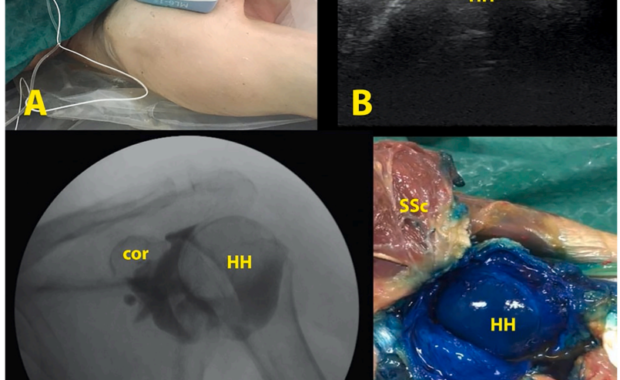

Pericapsular nerve group block for postoperative shoulder pain: A cadaveric radiological evaluation

Authors: Ece Yamak Altinpulluk, Ana Sofia Teles, Felice Galluccio, Diego García Simón, Marilina … Read more about Pericapsular nerve group block for postoperative shoulder pain: A cadaveric radiological evaluation